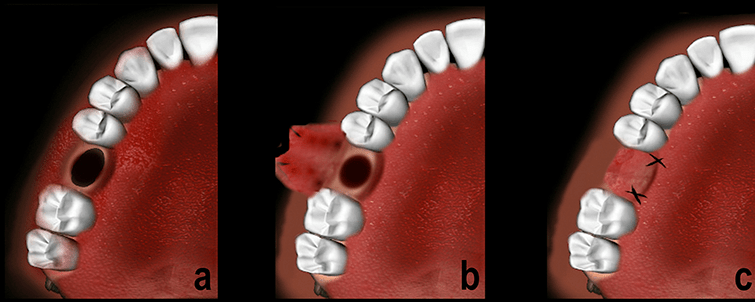

Buccal Advancement Flap

PALATAL ADVANCEMENT FLAP

• This technique is very similar to buccal advancement technique where the gingiva is close to the oroantral defect is mildly advanced to approximate it.

• May be done for small sized defects.

• It is not possible to get too much of advancement, as the palatal tissue is very rigid and thick.

• In this,the palatal tissue surrounding the OAC, is reflected +may be advanced downwards and sutured to the buccal tissue to cover the detect.

• Not a very successful procedure.

ROTATIONAL ADVANCEMENT FLAP or ASHLEY’S FLAP OPERATION:

• It is posteriorly based flap which gets its supply from the greater palatine artery.